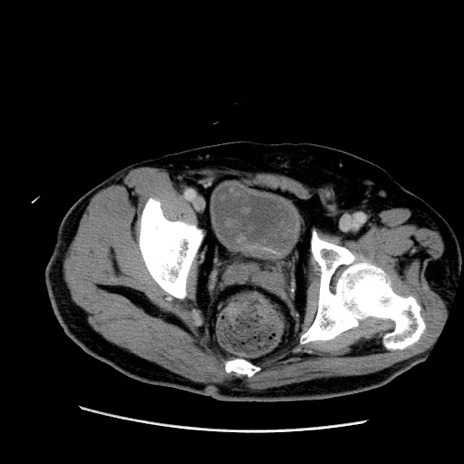

症例22(横断像)

【症例】50歳代男性

【主訴】腹痛

【現病歴】AVMからの被殻出血のため回復期リハ病棟入院中。 本日午後3時頃急に下腹部痛が出現した。

【既往歴】AVM、被殻出血、虫垂炎、高血圧

【身体所見】意識晴明、左半身不全麻痺、会話の理解は良好、36.5°C、腹部:膨隆、全体に板状硬、下腹部正中に圧痛点あり、反跳痛-、筋性防御不明、右下腹部にope scar

【データ】WBC 9400、CRP 0.06